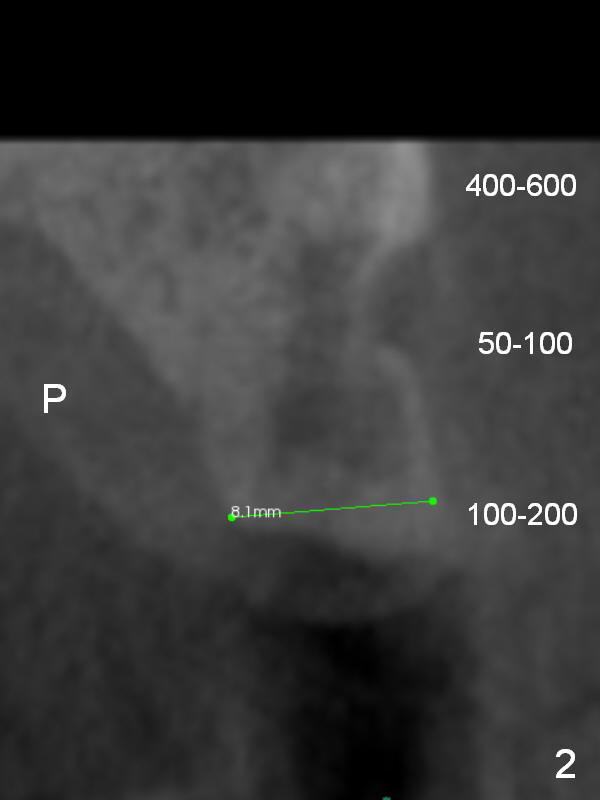

A 74-year-old man has diabetes. Implant osteointegration appears to be slow at #4, while the implant at #28 failed once. He requests implant at #13 (Fig.1). It seems that the bone is wide enough (8 mm, Fig.2 (CT coronal section) (P: palatal)) to hold a 4 mm implant (Fig.3 (axial section)). Since bone density is low at the coronal (100-200 units) and middle (50-100 units) segments (Fig.2), bone condensation will be beneficial. To facilitate wound healing, flapless approach is adopted using 1.6 mm pilot drill (Fig.4), followed by 1.4/2.6 mm bone expander. In fact there is resistance to expansion in the zone 1. Magic expander (3.0 mm) is also tried with difficulty. It appears that bone density is higher than expected. The second portion of Magic Surgical Kit is then used: 3.3 mm Magic Drill for 15 mm (gingival level, followed by Final Drill). A 4x13 mm IBS implant is seated incompletely. The osteotomy is further enlarged by 3.8 mm Magic Drill for 11 mm and deepened with 3 mm drill until 18 mm. Finally the implant is placed at a satisfactory level with insertion torque > 50 Ncm (Fig.5). A 4.5x4(3) mm abutment is placed and periodontal dressing is applied. The patient chooses to return for impression 6 months postop (Fig.6). The abutment changes to a 4x4(4) mm one. The crown is recemented nearly 2 years post cementation, which is related to distal and deep placement of the implant and bruxism (Fig.7).